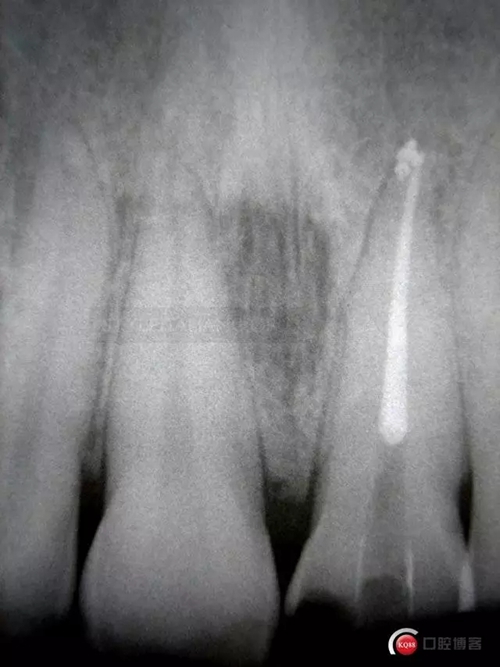

This is Italo, 32 years old, a few hours after a bicycle accident, coming from the hospital emergency room, on February 2006

The patient has a pulp hemorrhage on tooth 2.1 suffering for a deep palatal fracture

More than 5 mm fracture. Tooth 2.2 is still vital

So, after the root canal treatment under the dam with correct pulp chamber opening, a cleaning of the cavity access and a root filling level control